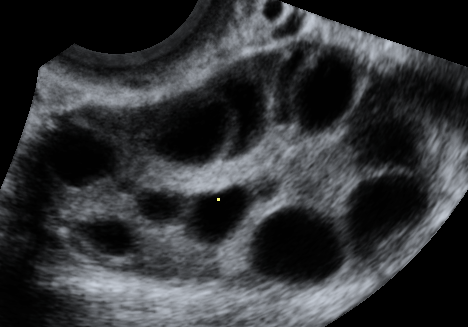

на узи как выглядят яичники? так: c855b1c22d11933eef4a39ab8b6d0a4a.png или так:e1f8a0c37cc200bbe12c0b005188f195.gif первое МФЯ, второе ПКЯ.

19.01.2015

как первое) Но так только на 7 д.ц, а на 15 там уже только доминантный и несколько мелких

значит не ПКЯ. при ПКЯ, как видно на картинке, фолликулы располагаются по краям в виде ожерелья. у меня так было.так что у тебя все нормально, МФЯ не страшно.пролактином занимайся))